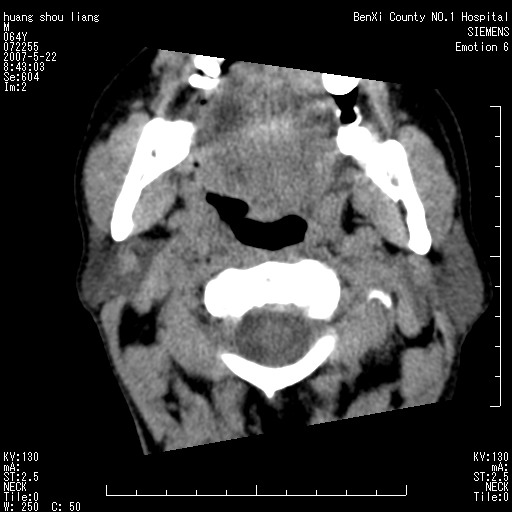

男性,64岁。颈部包块8年。最近增大。

对不起大家,可能是片子发太多有点乱,正常腮腺在下颌角的外侧,颌下腺在下颌体的中部内侧,本例在下颌角内侧偏下,和腺体一点关系都没有,从vrt和mpr上可以很明显看出来,再者肿块是好多粘连在一块的,大家在仔细看看,左侧可能也是吧,我还是考虑为肿大的淋巴结融合在一块,但性质??????

右侧腮腺下部均匀软组织密度肿块,外形不规则,与周围组织分界清晰,考虑右侧腮腺混合瘤或多形性腺瘤。

大家好,病理结果出来了,如大家所说,颌下腺混合瘤。

唉,解剖没学好吧,我诊断错了,不过还是有些不理解回去我在多看看书,谢谢大家的参与,以后我还会奉献好的病例。